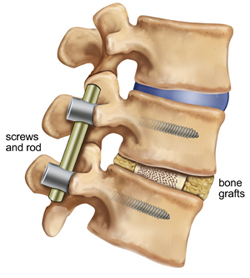

The nerve roots are then moved to one side and the disc material removed from the front (anterior) of the spine. A bone graft is then inserted into the disc space. The bone graft material acts as a bridge, or scaffold, on which new bone can grow. Screws and rods are inserted to stabilize the spine while the treated area heals and fusion occurs, and the ultimate goal of the procedure is to restore spinal stability.